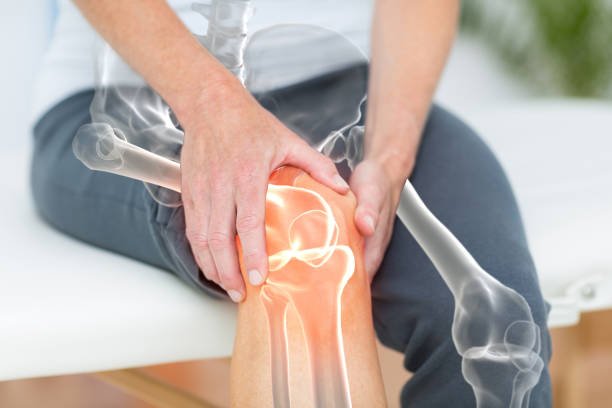

Joint replacement surgery has a profound impact on the quality of life for patients. It relieves chronic pain, enhances mobility, and allows individuals to return to their favorite activities. The reduction in pain and improved function often leads to increased physical activity, which can have a positive effect on overall health and well-being.

Patients who have undergone joint replacement surgery report a significant improvement in their ability to perform daily tasks, such as walking, climbing stairs, and even playing sports. This increased independence and mobility can have a profound psychological impact, boosting self-esteem and reducing the risk of depression associated with chronic pain and disability.